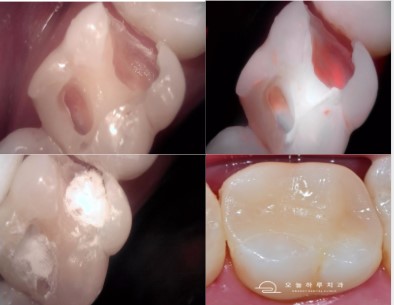

- 충치 제거 후 상태 확인

- 내부는 종이처럼 얇은 치질만 남은 상태

- 세균 활성도 확인을 위해 큐레이(Q-Ray) 촬영

- 신경 보호: MTA 적용

- 신경이 노출되기 직전 상태

- MTA(신경보호 재료)와 GI 재료로 2중 보호층 형성

- 온레이 제작

- 당일 구강 스캔 → 병원 내 기공소에서 밀링

- 바로 온레이 접착까지 완료 (원데이 보철 치료)

- 최종 보철물 부착

- 치아 색상과 유사한 온레이로 마무리

- 큐레이 촬영으로 적합도 최종 확인